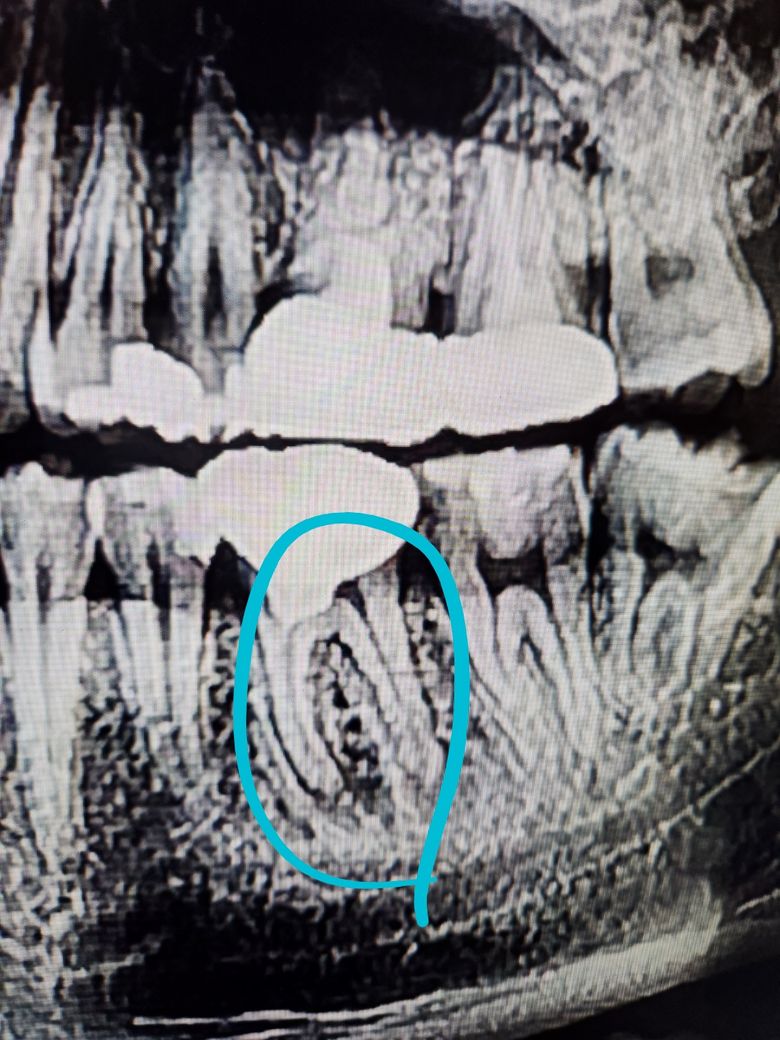

재신경치료해야해서 하늘색 동그라미 뿌리끝 염증인데 석회화로인해서 재신경치료 들어가야 합니다

사진 3장 각각 달마다 다른사진인데 염증이 커지는것같이 보이나요 아니면 다 비슷비슷하나요?

1. 사진 상으로는 염증이 커져보이는지에 대해서는 판단하기 어렵지만 염증의 경계가 불규칙한 것으로 보아 진행성으로 보여집니다. 치료를 하셔야 할 것으로 보입니다.

-염증의 크기는 차이가 없어 보입니다.